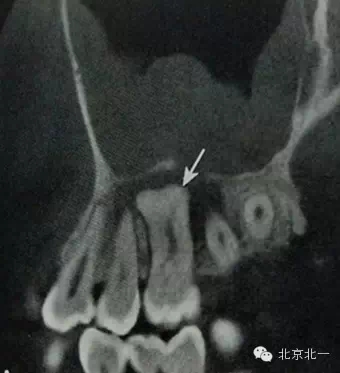

2)牙骨質(zhì)增生:

概述:

是由于齲壞、牙周炎、頜創(chuàng)傷等某些局部因素或全身疾患的影響,牙骨質(zhì)形成的異常增加。牙骨質(zhì)增生可發(fā)生于一個或者多個牙,多無臨床癥狀。

【CBCT表現(xiàn)】:

牙骨質(zhì)增生可表現(xiàn)為整個牙根體積的膨大,或僅表現(xiàn)為根尖呈球狀增生,對于多根牙,體積的膨大可局限于個別牙根,不伴根尖周感染的情況下,便便牙牙周膜及硬骨板影像相連續(xù)、完整。部分病例可見牙周膜間隙消失,牙根與牙槽骨粘連,導致牙齒萌出障礙或者滯留。

B6腭根根尖區(qū)膨大,牙周膜和骨硬板消失,根尖周見低密度影,上頜竇下壁骨質(zhì)不連續(xù),B B6頜面已開髓。